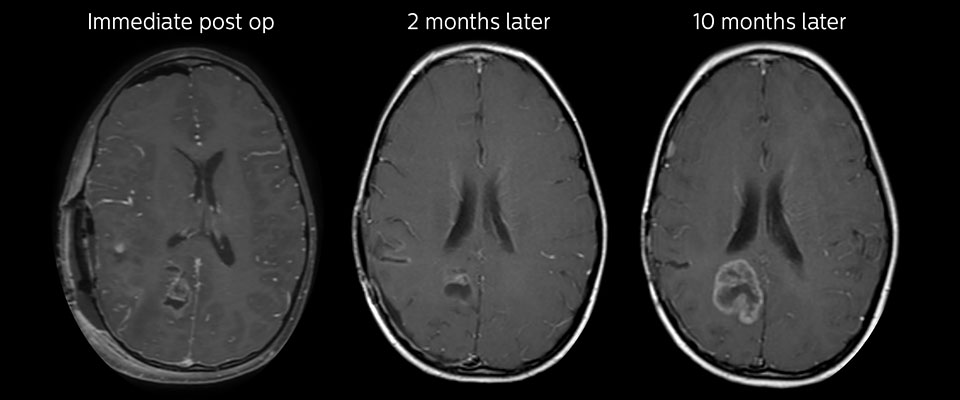

MRI with APT post resection

Immediately post resection MRI was again performed. T2-weighted and postcontrast T1-weighted images are quite inconclusive for distinguishing residual tumor tissue from postoperative tissue changes. On the APT image some high signal is still seen, which would suggest residual tumor tissue.

Follow-up over time

In later follow-up scans the post-contrast T1-weighted images suggest recurrent tumor growth. So, it would be interesting to study the predictive value of APT in a large patient group.